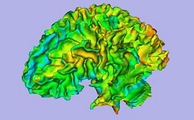

Result from the ARCTIC module in Slicer 3.6: cortical thickness map from pediatric MRI